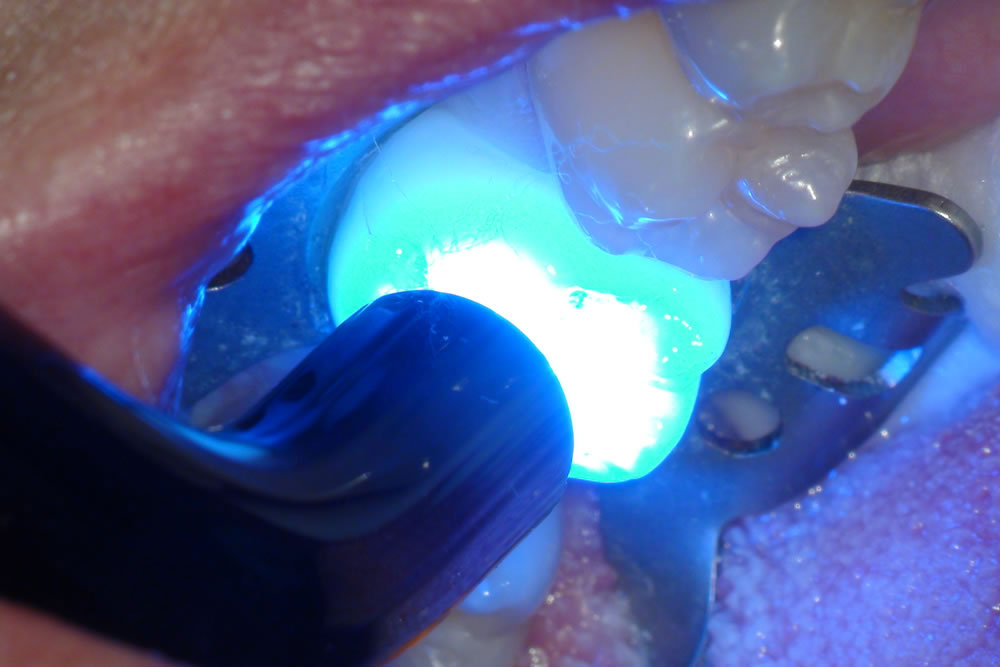

⑤光を当て硬化させる

CRは光によって固まります。この重合の際に目では見えないレベルですが、わずかに収縮を起こして固まります。そのため、できるだけ1度に重合する量を少なくし、収縮量を少なくする事で隙間ができないようにし虫歯の再発を起こりにくくします。※重合/複数の分子が結合して、分子量の大きな化合物を生成すること。

レジンという歯の治療に用いるプラスチックの材料を、当該歯に流し込み特殊な光を当てて固めます。(マイクロスコープの強力なライトでも固まってしまうので遮光のため、視界が黄色くなっています。)